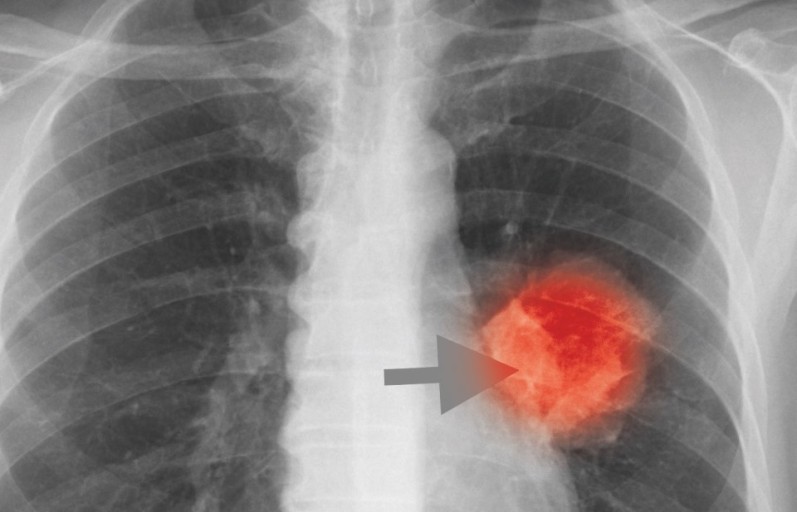

9. 흉부 고통

폐암에 걸리면 흉부에 고통이 느껴져요. 폐의 가장자리에 생긴 폐암이 흉막과 흉벽을 침범해서 고통이 생기는 것으로 가슴이 답답하면서 꽉 막힌 느낌이 지속되며 날카롭게 찌르는 듯한 느낌과 압력 하는 느낌 등 여러 가지 고통이 나타납니다.

폐암 초기증상 10. 상체 전반적인 고통

흉부 고통뿐 아니라 폐에 암세포가 상체 쪽으로 전이될 그럴 경우 상체 여러 곳곳에서 고통을 느낄 수 있어요.